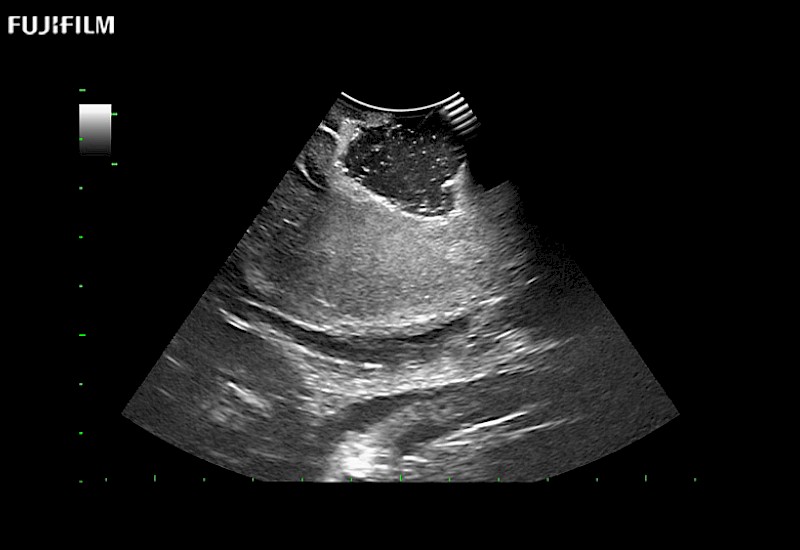

The world's only phased array burr-hole transducer that is ideal for scanning during burr-hole guidance procedures.

Main Specifications: